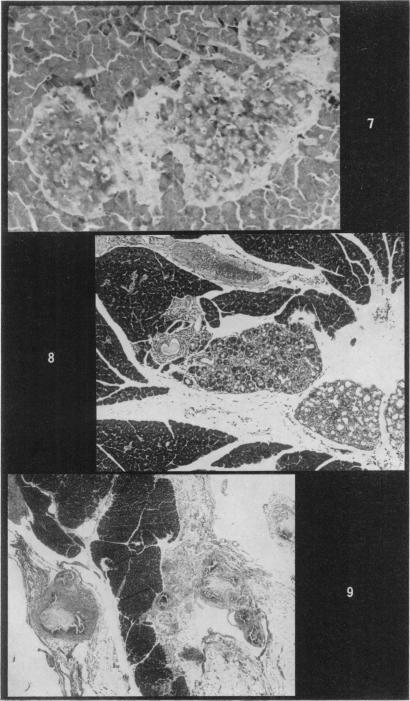

Repeatedly bred male and female rats develop hyperglycaemia, hyperlipidaemia, hypertension, arteriosclerosis and age prematurely. The intensity of these degenerative changes parallels the number and frequency of breedings. The islets of Langerhans undergo progressive hyperplasia and β-cell degranulation with each successive breeding. The pancreatic arteries are especially prone to develop arterial lesions which consist of abnormal mucopolysaccharide accumulation, elastic tissue breakdown, fibrosis and calcification. With continued active breeding the islet degenerative changes and arteriosclerosis become aggravated and many animals exhibit acinar necrosis, pancreatitis and parenchymatous calcification. It is believed that reproductive activity activates the hypothalamic-pituitary-adrenal-gonadal axis releasing hormones which have a dynamic effect on protein, fat and carbohydrate metabolism. In addition, unusual metabolic demands during such phases as gestation and lactation also effect protein, fat and carbohydrate metabolism leading to β-cell degranulation or “exhaustion” of insulin reserve.

反复繁殖的雄性和雌性大鼠会出现高血糖、高血脂、高血压、动脉硬化且过早衰老。这些退行性变化的强度与繁殖的次数和频率成正比。随着每次连续繁殖,胰岛会逐渐增生,β细胞脱颗粒。胰腺动脉尤其容易出现动脉病变,包括异常的粘多糖积累、弹性组织破坏、纤维化和钙化。随着持续的频繁繁殖,胰岛退行性变化和动脉硬化会加重,许多动物会出现腺泡坏死、胰腺炎和实质钙化。据信,生殖活动会激活下丘脑 - 垂体 - 肾上腺 - 性腺轴,释放对蛋白质、脂肪和碳水化合物代谢有动态影响的激素。此外,妊娠和哺乳期等阶段的异常代谢需求也会影响蛋白质、脂肪和碳水化合物代谢,导致β细胞脱颗粒或胰岛素储备“耗尽”。